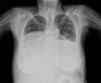

A 55-year-old woman arrived at the emergency room with dyspnea and generalized edema. The patient had as relevant medical history, a mechanical mitral valve, severe tricuspid regurgitation, pericardiectomy apparently due to recurrent pericardial effusion, atrial fibrillation and a pacemaker for complete atrioventricular block. Physical examination revealed signs of right-sided heart failure and tricuspid regurgitation. The chest X-ray (Figure 1), echocardiography and computed tomography (Figure 2) revealed a giant right atrium (18 cm×15.3 cm×16.3 cm) and giant left atrium (13.1 cm×9.6 cm×9.1 cm). Right and left ventricles had normal size and function. She also had severe tricuspid regurgitation and a normally functioning mitral prosthesis. The atria were so large that they were causing pulmonary restriction and dyspnea that was difficult to manage. The patient presented progressive deterioration during hospitalization and despite heart failure treatment she died.